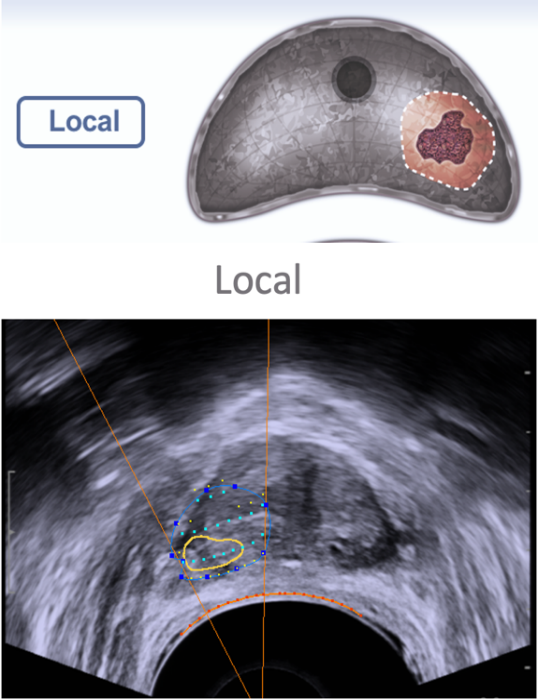

Biopsia de próstata por fusión guiada por TRUS-MRI

La siguiente innovación tecnológica de la biopsia de próstata guiada por resonancia ha sido el advenimiento de la fusión (o «registro») de hardware y software que permite la orientación en tiempo real al registrar y superponer las imágenes de mpMRI mapeadas previamente adquiridas en las imágenes TRUS durante la biopsia. Típicamente, esto se hace delineando (o «mapeando») el margen de próstata y la lesión sospechosa en las imágenes de mpMRI. Estas imágenes se transfieren posteriormente a una estación de trabajo especializada. TRUS toma imágenes de todo el volumen de la próstata, y el software fusiona las imágenes de resonancia magnética y de ultrasonido de la próstata mediante el uso de los límites como una guía (utilizando un método fijo y / o flexible). Posteriormente, el hardware monitorea la posición de la sonda TRUS con respecto a la próstata y puede proporcionar imágenes en tiempo real para alinear la biopsia con el sitio registrado de la lesión objetivo. (Figura 4)

Fig. 4. Biopsia por fusión. Imagen de fusión con objetivo (izquierda). Tecnología organ based tracking para control del disparo (derecha)

En comparación con el registro cognitivo, esta técnica potencialmente ha mejorado la reproducibilidad al disminuir la dependencia del médico a la interpretación de la resonancia. Sin embargo, esta técnica requiere hardware y software especiales, capacitación e implementación meticulosa. Rara vez se visualiza la lesión de las imágenes de ultrasonido. Sin una imagen de ultrasonido que se correlacione con la anormalidad de la resonancia magnética, la precisión de esta técnica depende de numerosos factores técnicos, que pueden hacer que la focalización sea subóptima. Las limitaciones de esta técnica incluyen los costos adicionales del hardware y el software, la precisión del software de fusión, la precisión de la localización espacial de la sonda TRUS y la curva de aprendizaje y la capacitación asociadas.